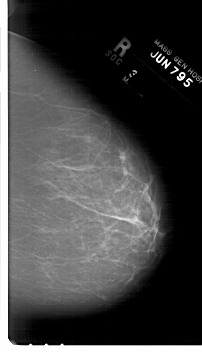

A_1719_1.RIGHT_MLO

DATE_OF_STUDY 7 6 1995

PATIENT_AGE 45

DENSITY 2

LEFT_MLO LINES 6661 PIXELS_PER_LINE 4171 BITS_PER_PIXEL 12 RESOLUTION 43.5 OVERLAY

RIGHT_MLO LINES 6616 PIXELS_PER_LINE 4036 BITS_PER_PIXEL 12 RESOLUTION 43.5 NON_OVERLAY